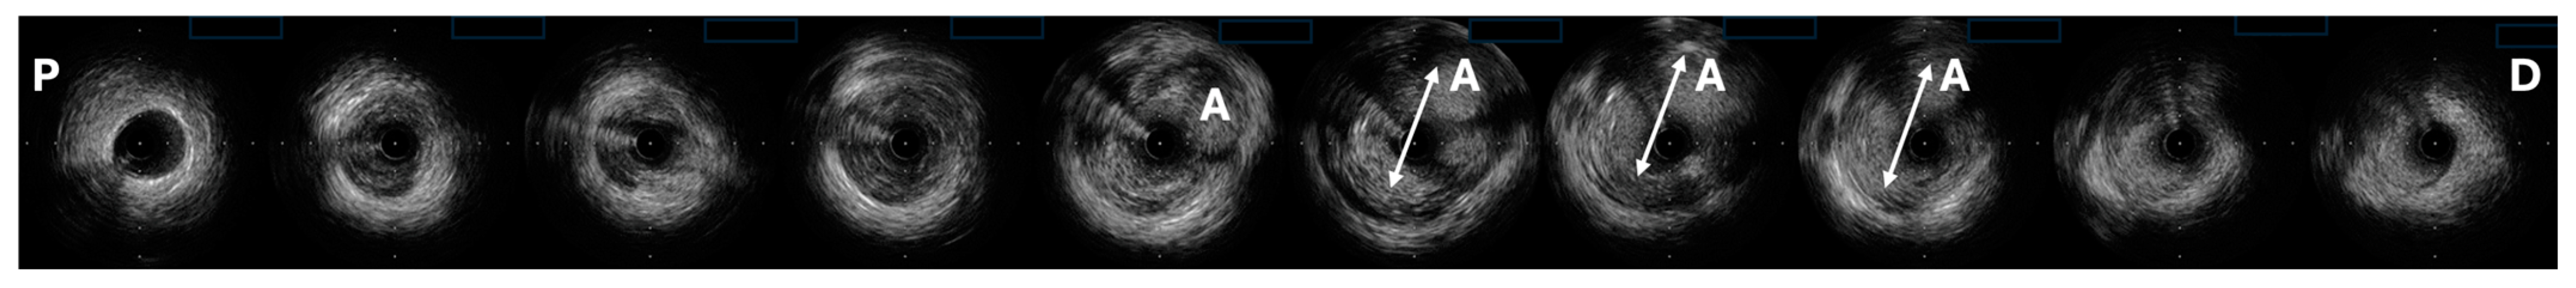

- Manginas, A.; Cokkinos, D.V. Coronary artery ectasias: Imaging, functional assessment and clinical implications. Eur. Heart J. 2006, 27, 1026–1031. [Google Scholar] [CrossRef]

- Iwańczyk, S.; Smukowska-Gorynia, A.; Woźniak, P.; Grygier, M.; Lesiak, M.; Araszkiewicz, A. Invasive assessment of the microvascular coronary circulation in patients with coronary artery aneurysmal disease. Pol. Arch. Intern. Med. 2023, 133, 16392. [Google Scholar] [CrossRef] [PubMed]